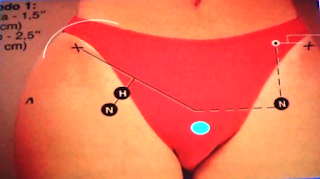

PUNTOS DE PALPACIÓN: espina iliaca anterosuperior, sínfisis del pubis.

La mejor manera de saber dónde se encuentra la articulación de la cadera es

ubicando el punto medio de una línea imaginaria que une la cresta iliaca

anterosuperior y la sínfisis del pubis. De este punto medio a tres o cuatro

travesees de dedo se encuentra con seguridad la articulación de la cadera.

De forma un poco más práctica para ubicar el punto central de la cadera podemos palpar la sínfisis del pubis y seguir la línea imaginaria transversa (de PITERS), que une la sínfisis del pubis con el trocánter menor. Es evidente que esta línea une las dos trocánters. Para ubicar la cadera primero debemos ubicar el punto medio de esta línea imaginaria y a dos o tres travesees de dedo encontraremos la cadera.